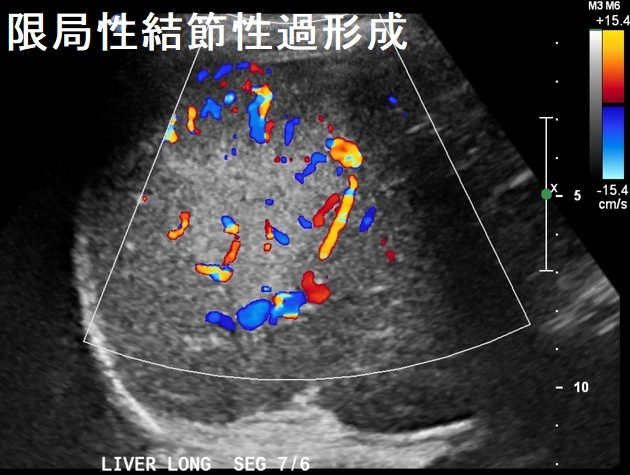

限局性結節性過形成(focal nodular hyperplasia:FNH)は、良性肝腫瘍の一つです。30~40歳代の女性に多く、37.8%で経口避妊薬の内服歴あり。ほとんどの場合、無症状で偶然発見されます。

肝細胞癌や転移性肝癌とは血管構造が異なるため、腹部超音波検査のドプラーモードやダイナミックMRI・CTで鑑別されます。限局性結節性過形成(FNH)では、特徴的な中心性瘢痕があり、車軸状に造影剤が拡散します(車軸状血管)。